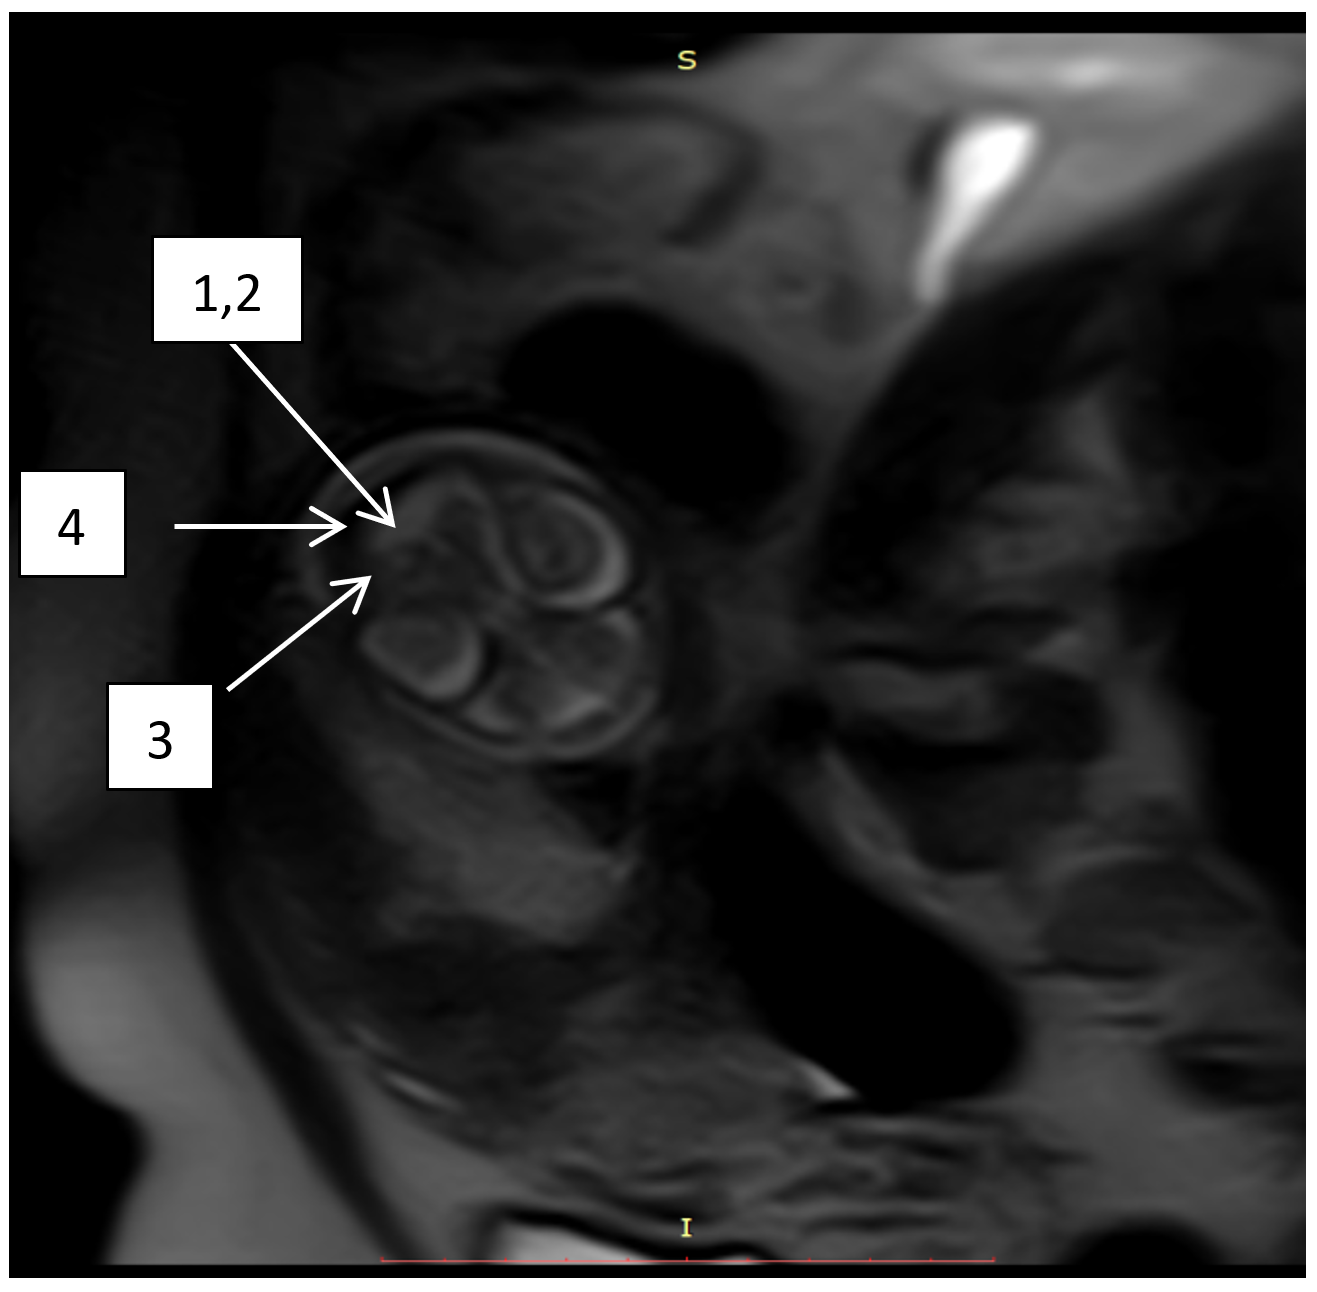

Рисунок 3 - МРТ плода в сагиттальной проекции Т2 ВИ:

1 - гипоплазия червя мозжечка; 2 - расширение межполушарной щели мозжечка; 3 - уменьшение межполушарного диаметра мозжечка; 4 - расширение мозжечково-мозговой цистерны